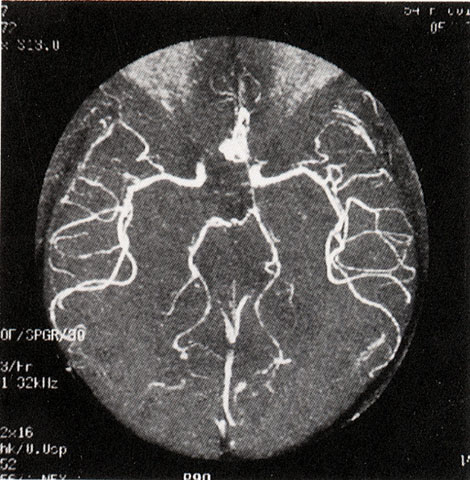

FH1042 脑动脉瘤(MRA)

图  名 脑动脉瘤(MRA)